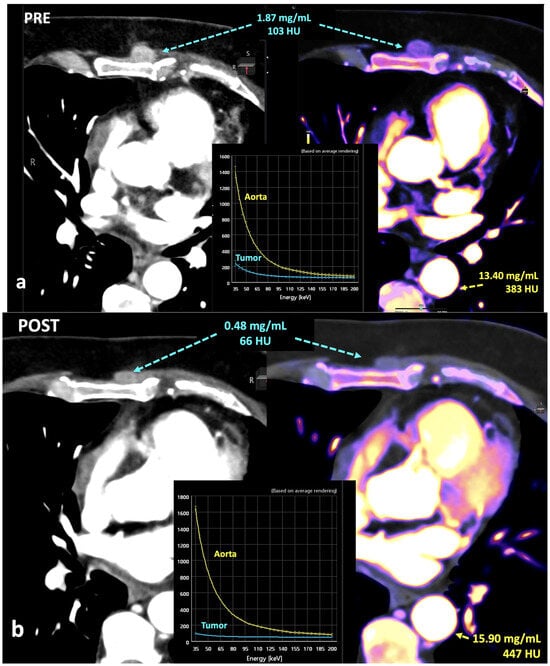

Fourth, the measurement of iodine concentration also depends on the contrast injection protocol, the time of acquisition, or factors from the patient themselves, such as cardiac input. The timing of image acquisition must be considered to avoid false-negative errors based on iodine quantification in slower and/or lesser enhancing lesions (i.e., papillary renal cancers). Iodine quantification is not a dynamic parameter, and only represents the amount of iodine contrast uptake within an object with a concrete timing following the administration of iodine contrast (Figure 18).

In this setting, normalization to vessels could be a solution for a quantitative assessment of iodine concentration but the published data are discordant in this regard. Normalization can mitigate variability reducing physiological fluctuations in iodine distribution by using normalized iodine calculation, which represents the iodine concentration in an object divided by the iodine concentration in in a reference vessel such as the aorta [55,56] (Figure 19). Nevertheless, after normalization, the scanner type still has a significant effect on iodine variability in the pancreas and liver. Lennartz et al. [56] reported that iodine concentration also showed differences in variability between scanner types depending on the organ studied, with the least variability in the kidneys and highest variability in the liver [55,56].

Breast cancer recurrence treated with hormotherapy and kinase inhibitors evaluated with DECT pre- (a) and post-therapy (b). A decrease in density and iodine concentration in the lesion is evident following therapy (b). Also note the different density and iodine concentration of the aorta in both studies, a difference in enhancement that in many cases might alter the degree of significance of the changes seen in the lesion.